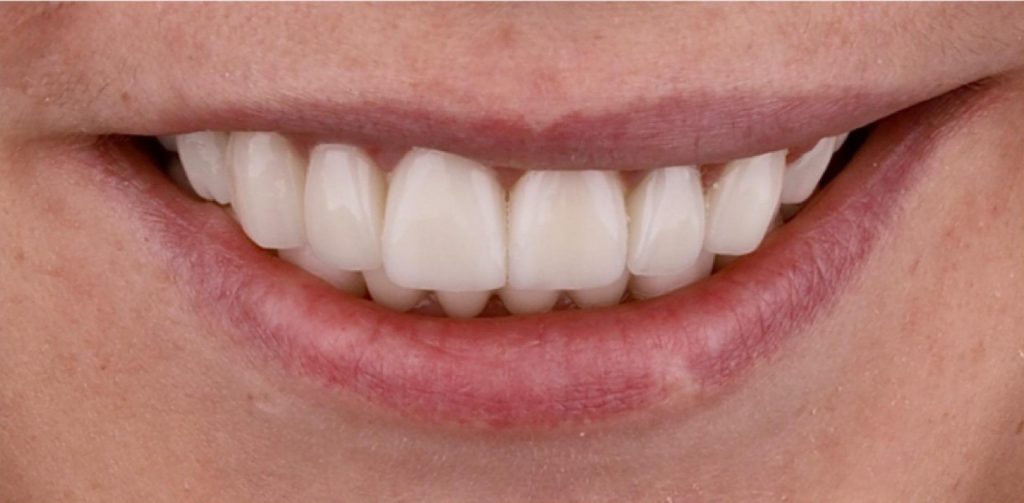

Tak Pacjentka skomentowała uzyskany efekt: “Od zawsze marzyłam o takiej zmianie, żałuję, że nie zdecydowałam się wcześniej”.

Prace protetyczne odbywały się we współpracy z Laboratorium Dental Scan, ściślej z Panią Anną Simierską i Agatą Łatyk-Banasik.

Cała terapia, jak zawsze w takich przebudowach, nawet częściowych wiąże się z bezwzględnym zwieńczeniem wykonania szyny ochronnej, której konstrukcja jest zawsze uwarunkowana indywidualnie. Zalecenia jej noszenia przez lekarza również są indywidualne i mogą się zmieniać w perspektywie czasu.

Tak wyprowadzony Pacjent powinien stawiać się (oczywiście zawsze z szyną) na wizytach kontrolnych co 6 m-cy. W międzyczasie z zaleceń lekarza z pewnością wskazane mogą być zabiegi higienizacyjne u naszych Pań higienistek, by podtrzymać u Pacjenta zdrowy stan przyzębia.